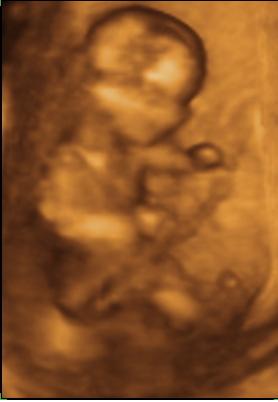

31 hetes